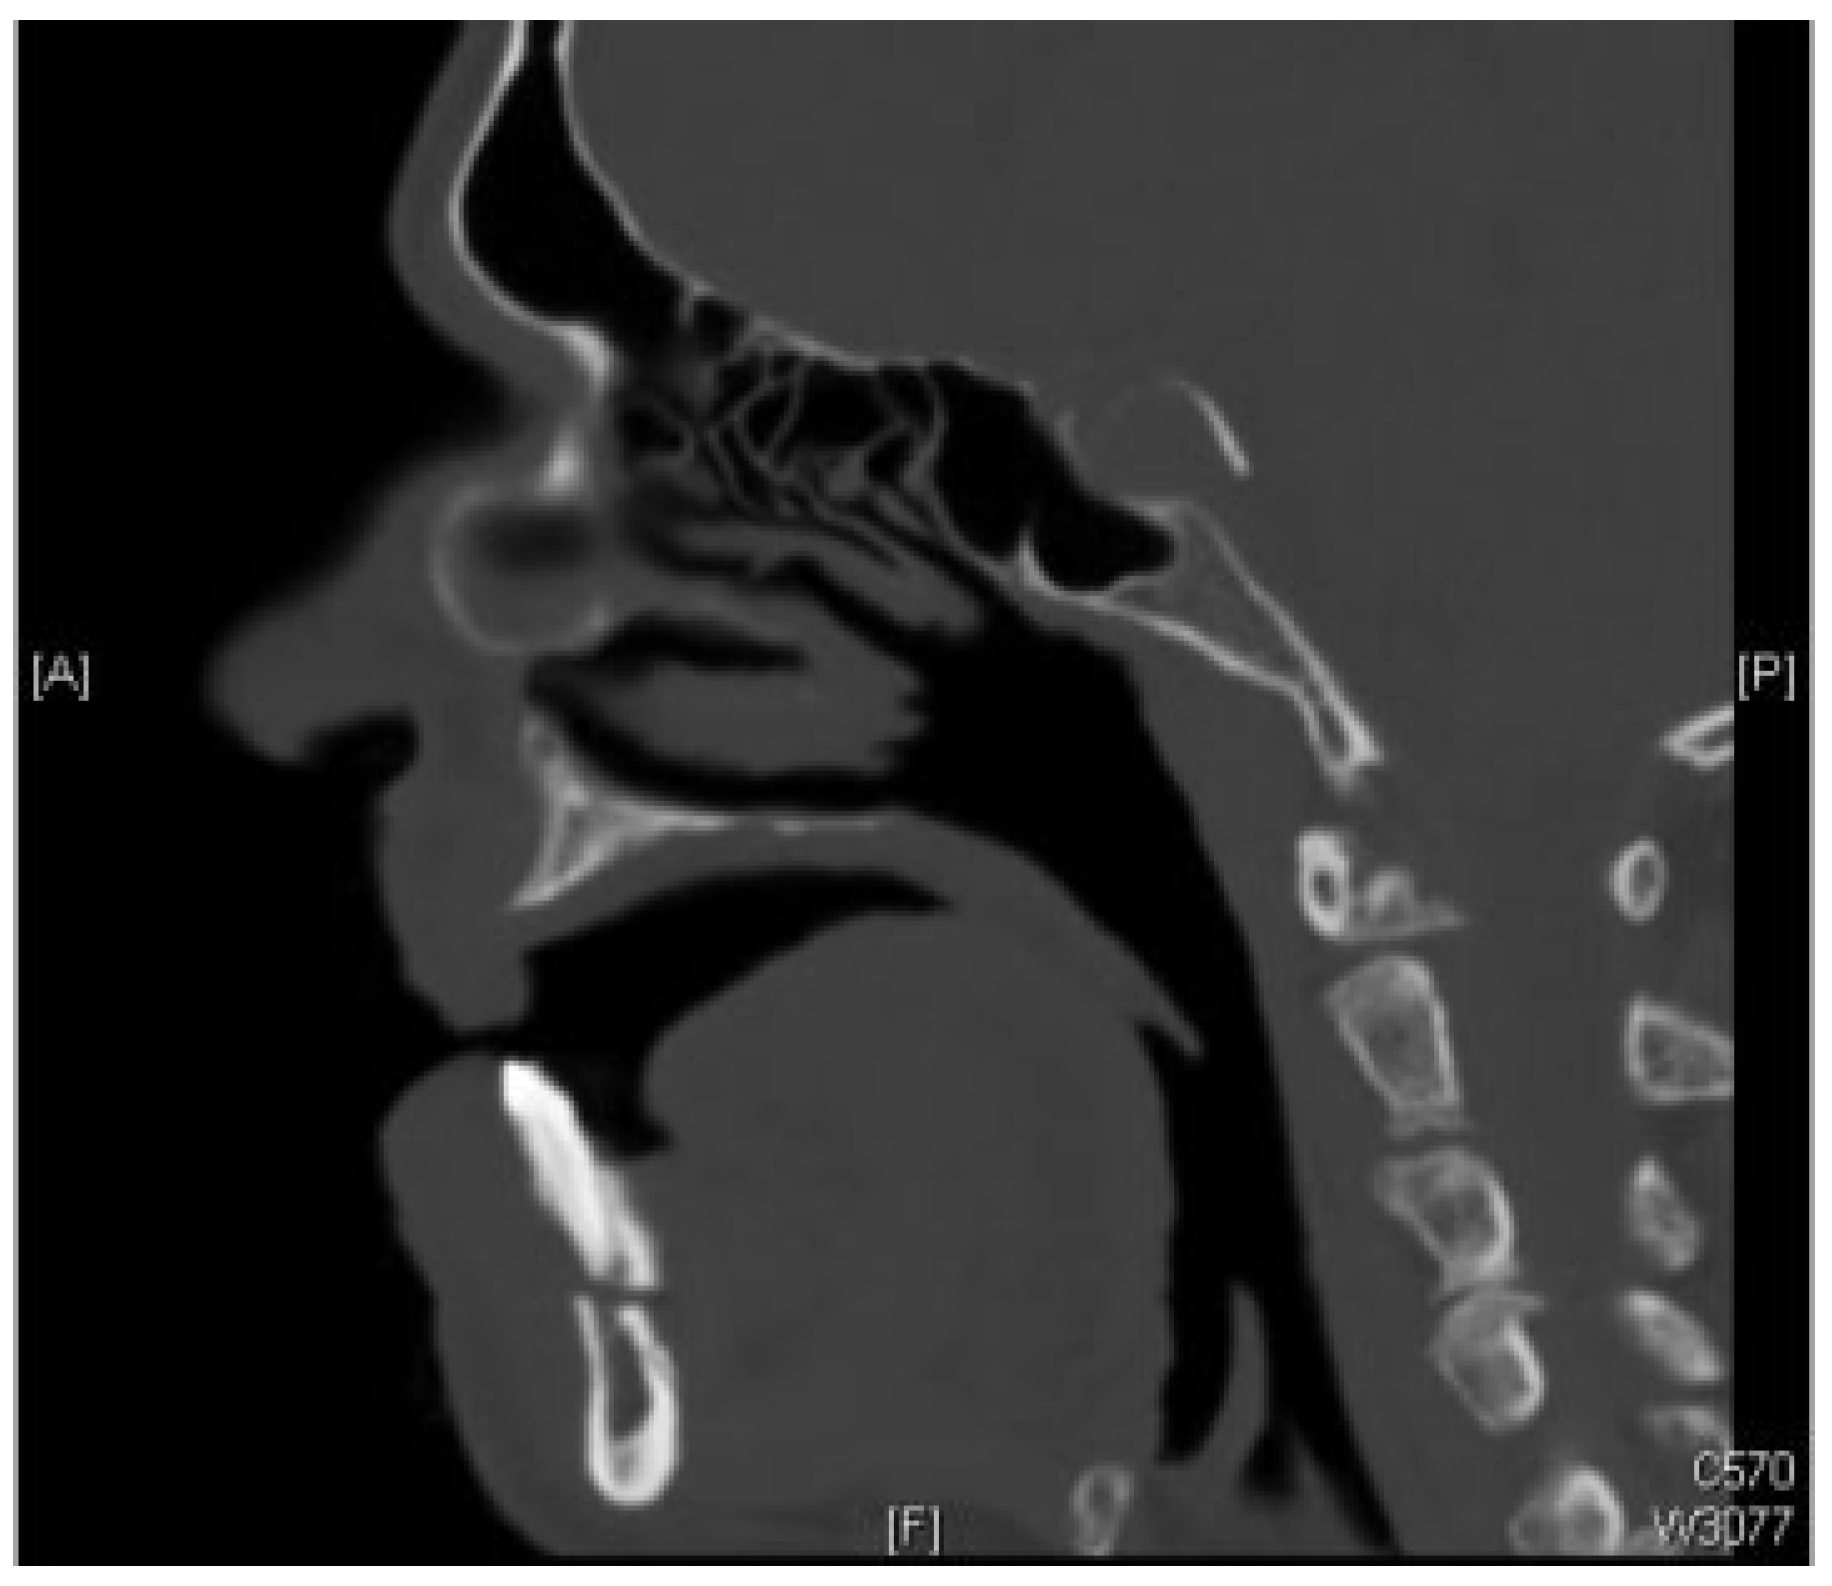

2.1. Case 1

2.2. Case 2